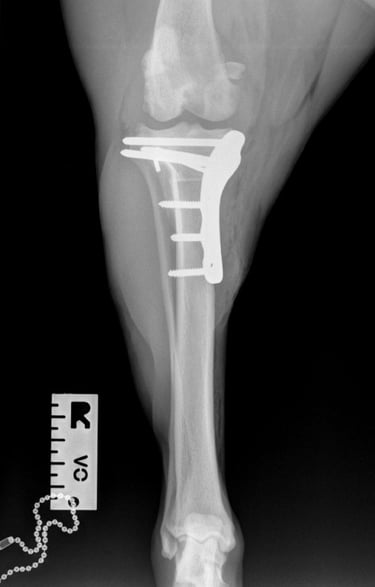

Postoperative radiographs showed that the proximal screw of the distal fragment is slightly longer than expected, but this is not anticipated to cause clinical issues. GImplants are in good position, there is correct compression and alignment is also optimal.

Postoperative TPA measured at 4.3°.

At the first postoperative recheck (day 3), Luna was nearly fully weight-bearing with only mild lameness. The surgical site showed excellent healing and 6 weeks post-op xrays (Figs. 7 and 8) show good ossification of osteotomy line and good position of implants.

Fig. 7

Fig. 8